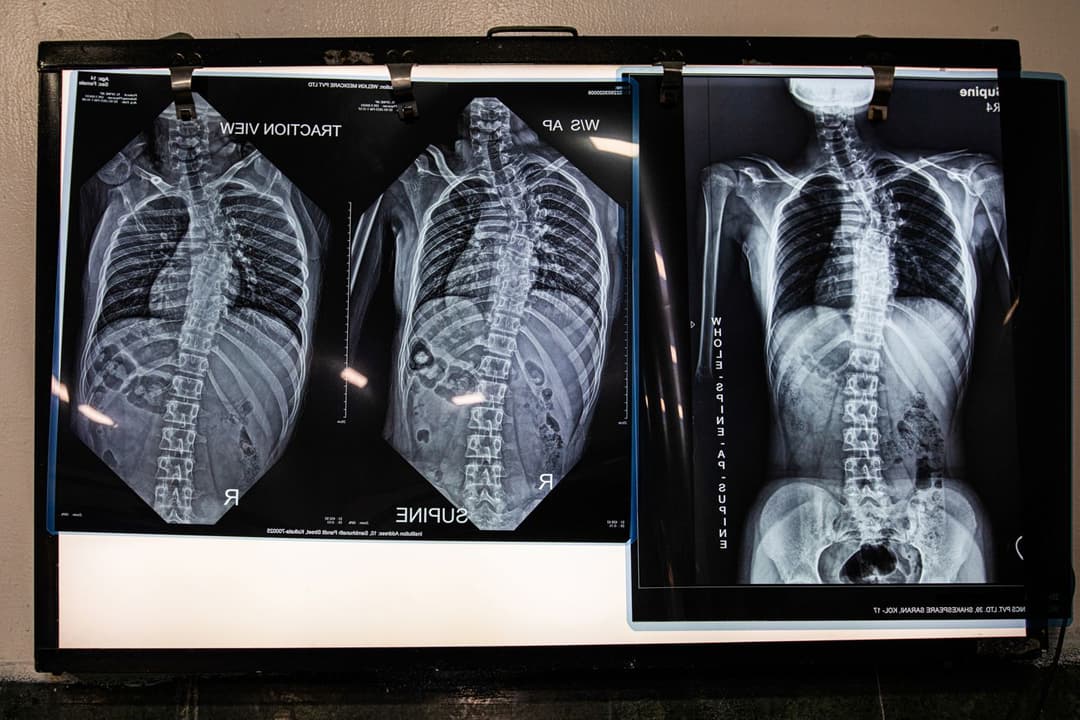

Roshan’s scoliosis was diagnosed when he was 21, and he was told he would never dance. Scoliosis causes the spine to curve sideways. Everybody has regular curves in their spines, but in kids and teenagers with it, the spine – or parts of it – curve abnormally in the shape of an ‘S’ or ‘C’.

The teenage Sebanti travelled from her home in South 24 Parganas to Kolkata to have surgery for adolescent idiopathic scoliosis (AIS). The procedure involved the insertion of two rods and 14 screws in her back to straighten her spine.